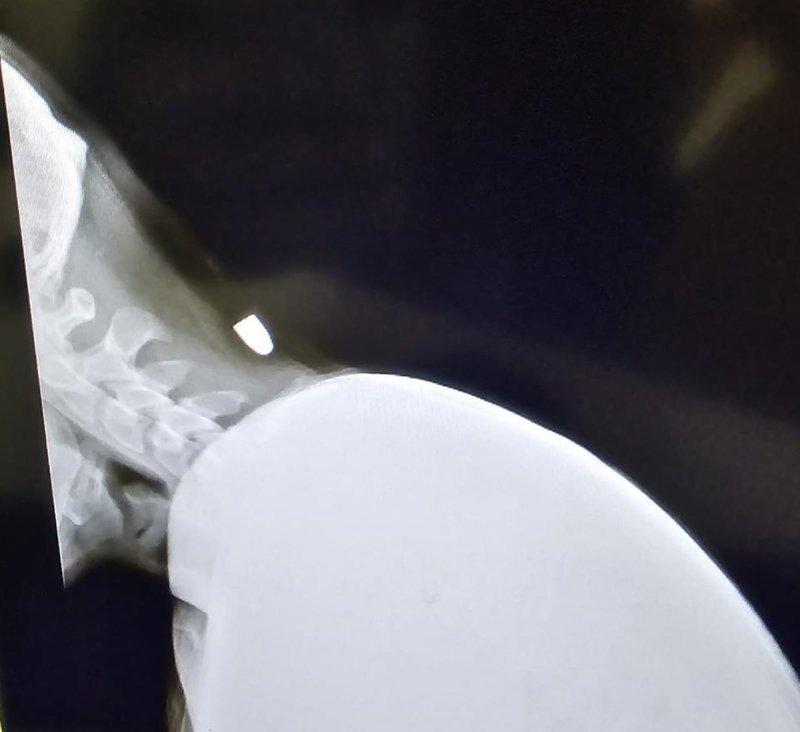

Aniden ensesinde ağrı hisseden Yavuz, yere yığılmasıyla arkadaşları tarafından hastaneye götürüldü. Hastanede yapılan müdahalelerde Yavuz'a ensesine mermi isabet ettiği tespit edildi. Geçen Pazartesi günü ameliyat olan Yavuz’un ensesindeki mermi 40 dakikalık ameliyatla çıkarıldı. Hastaneden taburcu edilen Yavuz'un sağlık durumu gün geçtikçe iyiye gidiyor. Polis ekipleri de konuyla ilgili inceleme başlattı.

Arkadaşlarıyla otururken yorgun merminin isabet ettiğini dile getiren Yunus Emre Yavuz, “İşte çalışıyorduk ve mola verdik. Akşam 19:30 sularında otururken biraz eğildim. Eğildiğim anda merminin düşmesi bir oldu. Biri sanki sertçe sopayla vurmuş gibi hissettim. Arkadaşlar yaraya baktığında kurşun olduğunu gördüler. Hastaneye götürdüler. Röntgen ve filmlere bakıldığında mermi olduğu anlaşıldı. Hastane sürecinde; röntgen ve MR filmleri çekildikten sonra ameliyat olmalısın dediler. Geçen pazartesi ameliyata girdim ve 40 dakika sürdü. Şükürler olsun sağlam çıktım. Kurşunu da incelenmesi için Adana'ya gönderildi. Zorlu bir süreç oldu ama atlattık” dedi.